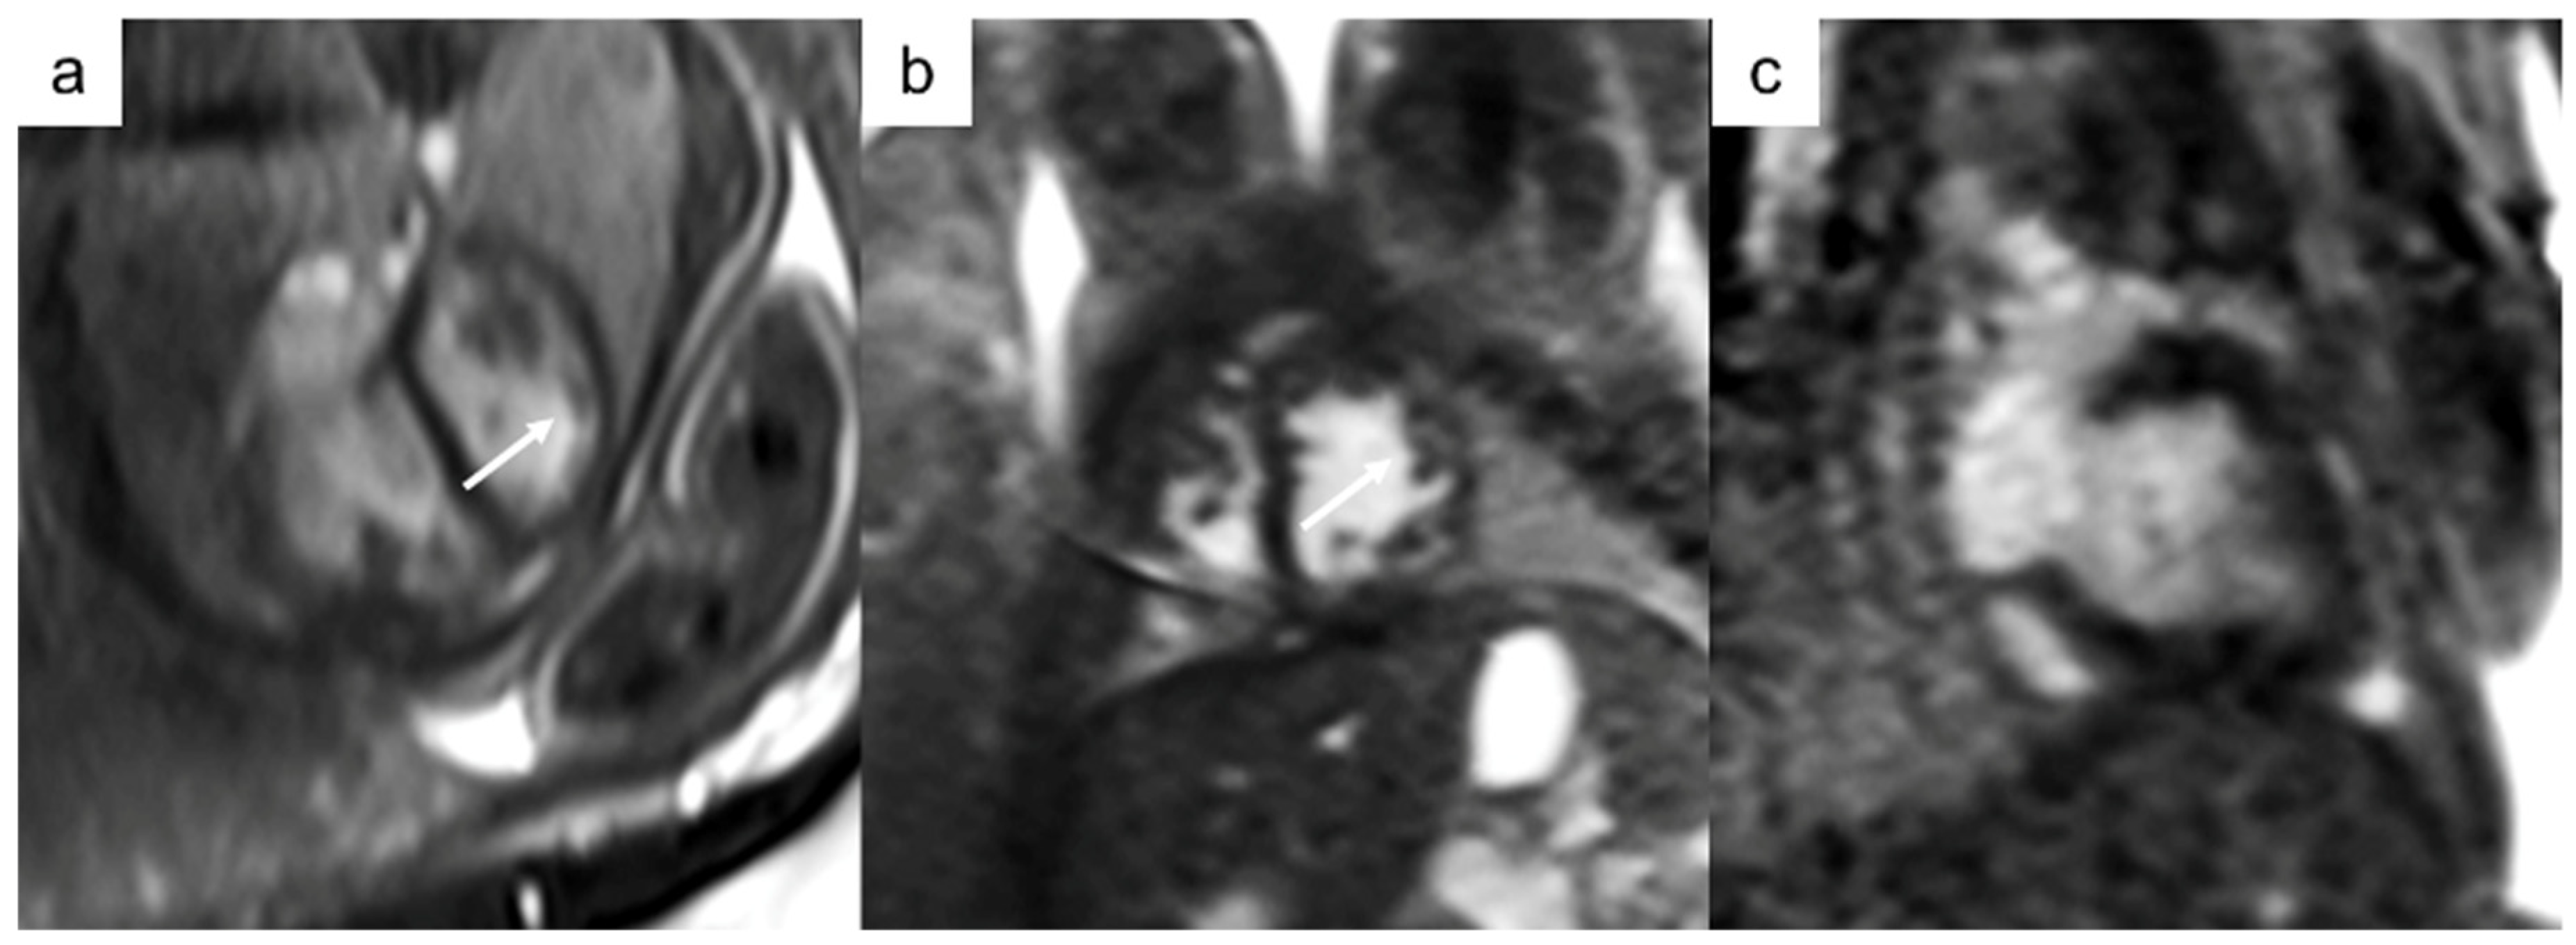

| Cardiac masses | -Assessment of function, size of mass, and relation to neighboring structures -Potential of tissue characterization -Renal and brain assessment in tuberous sclerosis |